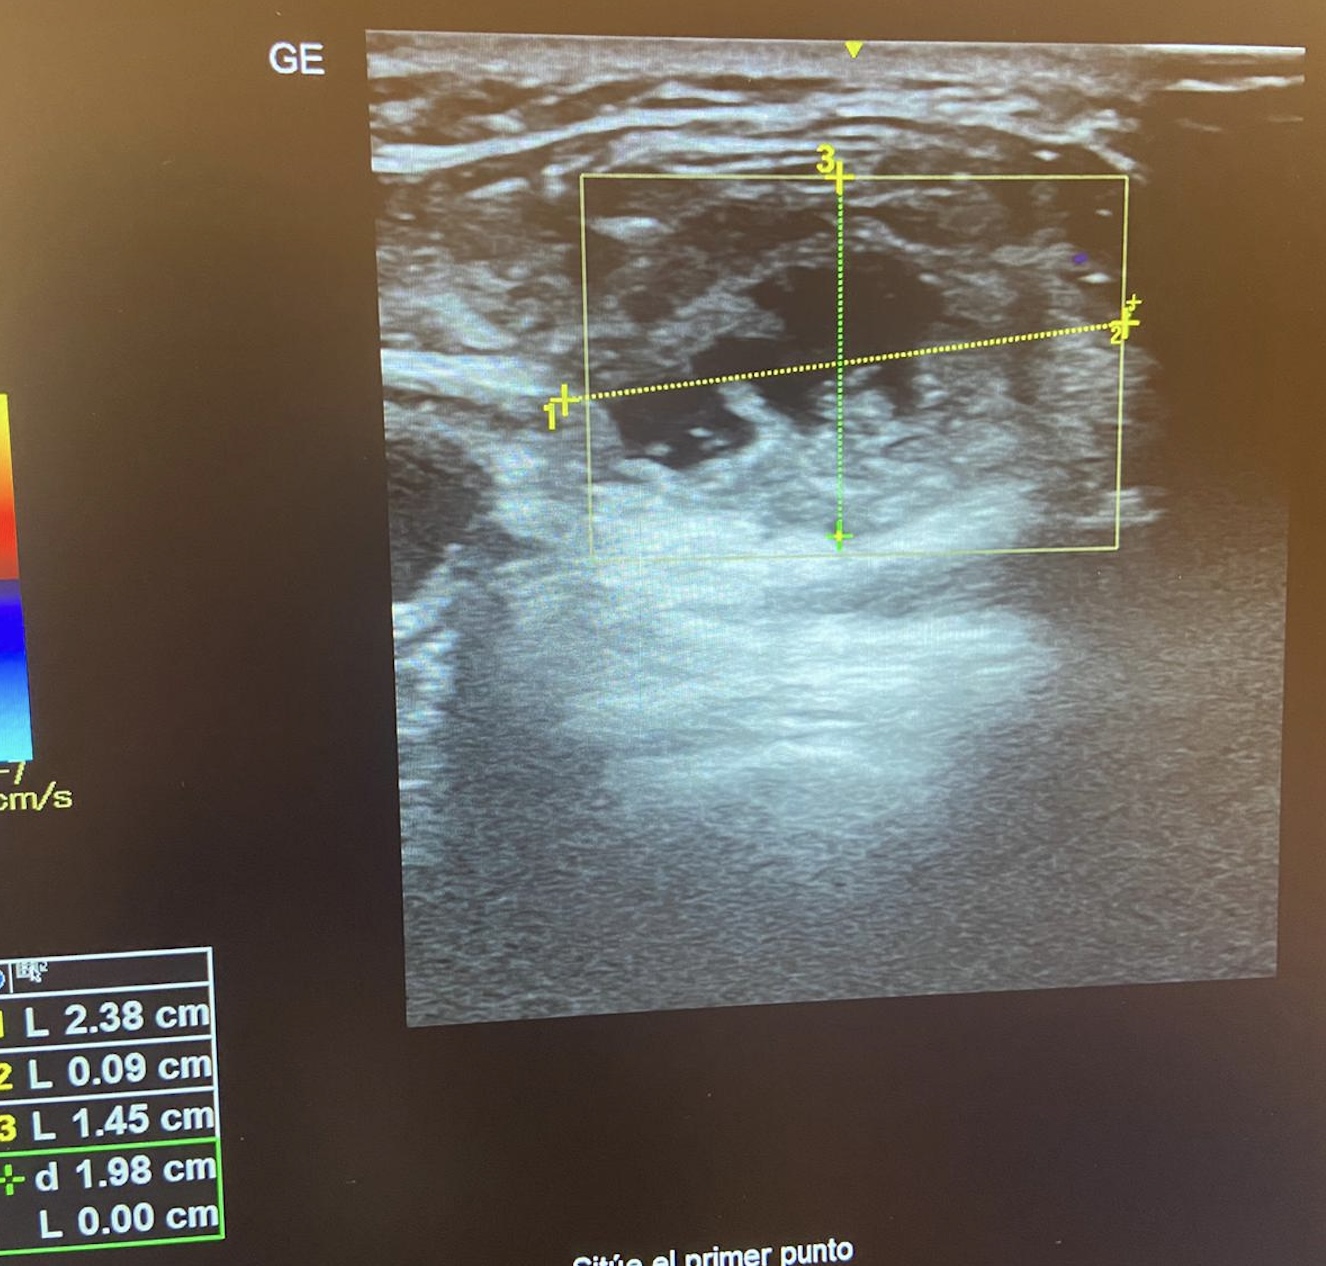

• Ecografía clínica: En tiroides dos imágenes a nivel de istmo/Lóbulo derecho tipo coloide (0,25 - 0,29) cm. Imagen de 2,38 x 1,45 cm bien delimitado, redondeada, con interior heterogéneo (hipo/hiper/anecoico). Doppler negativo.

• Juicio clínico: Adenopatía secundaria a carcinoma escamoso de cavidad oral.

• En hospital: Tras ser valorada por ORL de Guardia, se realizó Ecografía por Radiólogo (“Lesión quística laterocervical izquierda que sugiere quiste del segundo arco branquial complicado”) y TAC de cuello (“Adenopatías patológicas en nivel IIB laterocervical izquierdo (probablemente neoplásicas)”). Tras dichos hallazgos se realiza BAG: “Neoplasia escamosa”. Y tras pedir PET-TAC (Adenopatía compatible con actividad neoplásica) y revisar en consulta, detectan lesión oral que se biopsia: Carcinoma Escamoso. T1N2bM0. Realizando Glosectomía parcial + vaciamiento ganglionar izquierdo.